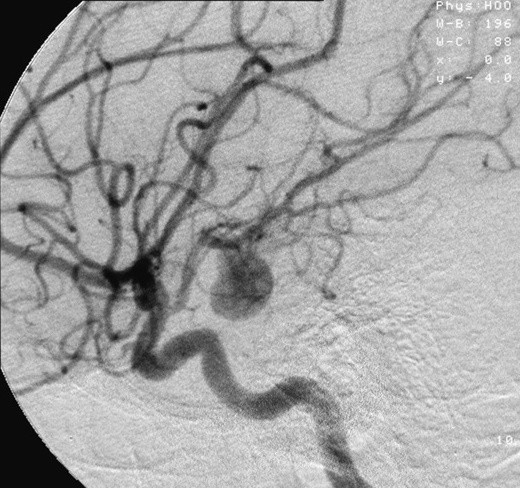

Diagnoza była druzgocąca: tętniak mózgu.

Lekarze nie panikowali jednak, bo byli przekonani, że operacja rozwiąże problem i nie powinna nieść ze sobą żadnych komplikacji. Niestety, doszło do powikłań, w wyniku których kobieta zmarła. Odeszła dwa dni po przyjęciu do szpitala.